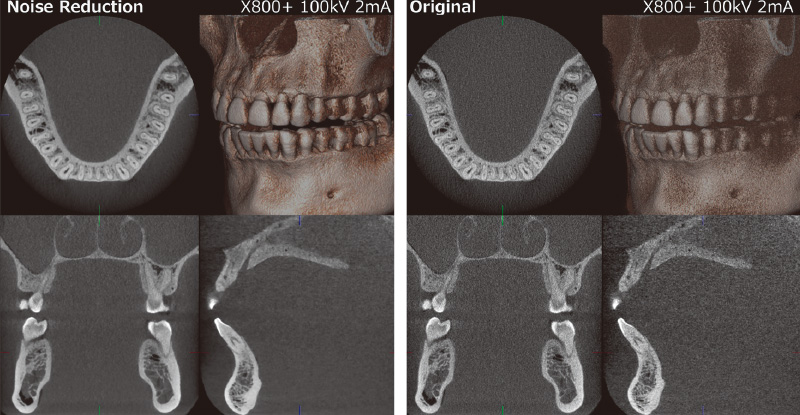

杉原 先述したように、フラットパネルの開発時点からあらゆるノイズを低減した上で最適化を行っています。「X800+」に搭載された「ノイズリダクションモード」(以下:「NRモード」)は、これまでのノイズ処理とは全く別の部分で行われていて、その詳細は独自ノウハウのため、この場でお話できないのが残念です(図3)。

田中 解像度をできるだけ下げないでノイズを減らす処理において、計算に非常に時間を要します。開発当初はその処理に数十分必要でしたが、検証と改良を重ね高速化を実現できたことで、現状では最大サイズでも1分を切るところまで短縮できました。その過程で、複雑な処理を適切に行うパラメーターを大量に決めていく必要がありました。最適なアルゴリズムを検討し、様々な改良を加えた新たな機能として、「ノイズリダクションモード」が「X800+」には搭載されています。

新井 高解像度を目指すとノイズが増えてしまう矛盾を、独自の発想と技術で払拭できたことによる臨床的な意義はとても高いと思います。「NRモード」を使用すると、被ばく線量はかなり抑えられるのではないでしょうか。

杉原 おそらく1/2以上は抑えられると思います。近年、第二次性徴期にあたる方の場合、線量を通常より下げることを推奨するガイドラインが示されましたが、まさにそうしたケースに効果を発揮するのではないでしょうか。

桐村 はい。これまでモリタでは一貫して低線量を謳ってきたのに、FOVを拡大しX線を多く照射することは、その基本コンセプトに反してしまいます。そこで私たちは、大きなFOVでも低い線量設定で撮影できることを追求しました。それは単に大領域における低線量撮影だけでなく、小領域の高分解能撮影においても増加しがちな画像ノイズを大幅に抑える効果があり、細部の表現力を保ったまま、全体的にもクリアな画像を提供します。これは画像生成に関わる多くのパラメータを、撮影条件に合わせて調整する独自のノウハウでもあります。

桐村 新しい製品を上市した際に、「前の画像の方が良かった」というご意見を耳にすることがあります。これは単に物理的な画質性能だけを追求していると、「診断に適した画作りが維持できているか」という重要なポイントを見失う場合があるということです。ですから、私たちとしては、あえて「X800」と同等の画像を追求したうえで、プラスアルファを提供する機能として「NRモード」を位置付けていますので、お好みに合わせて「NRモード」のON・OFFを切り替えることができるように設計しました。

![[写真] ノイズリダクションモード](/academic/dentalmagazine/wp-content/uploads/sites/2/2025/11/195-12_photo03.jpg)

図3 「ノイズリダクションモード」は、線量を抑えながら高解像度の画質を追求した結果生まれた機能。 -